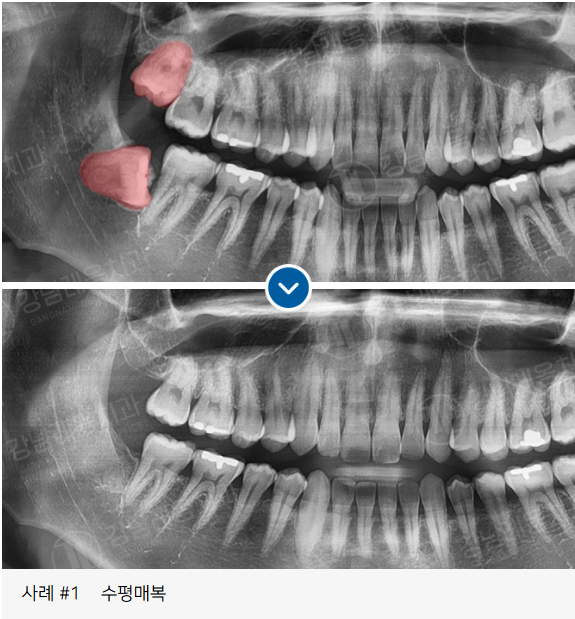

✅ 잇몸 속에 완전히 묻혀 있는

✅ 옆으로 누워있는 수평 매복 사랑니

고난도 케이스 경험 다수

사랑니 발치로 강남레옹치과에 방문해주시는

40~50%가 수평/매복 사랑니이며

아래와 같은 고난도 케이스도

충분한 상담을 통해

사랑니 진료를 진행하고 있습니다.